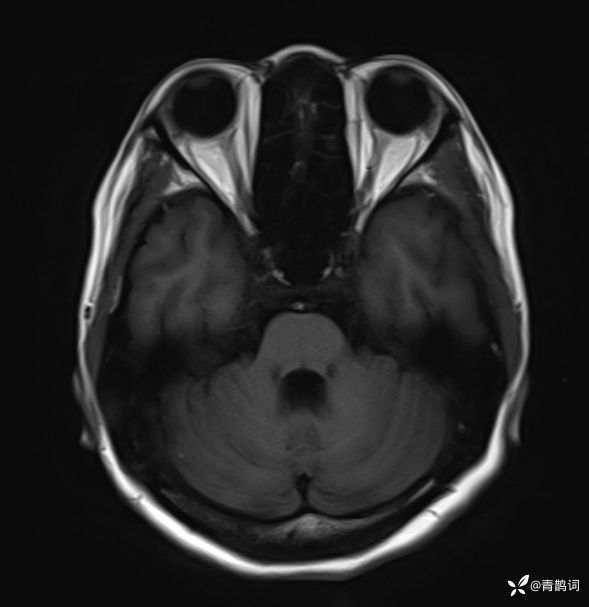

病例分享 | 45岁女患,7年的病史,结合影像学,如何诊断?

1、患者:女, 年龄:45岁

2、主诉:走路不稳渐加重7年,饮水呛咳伴头晕2年渐加重。

3、简要病史:患者于入院前7年出现走路不稳,表现为行走右偏,逐渐加重,易跌倒、不能自理;近2年出现饮水呛咳、吞咽困难及头晕;病程伴有耳鸣、反应迟钝,无恶心、呕吐。既往否认高血压、否认糖尿病、否认冠心病。

4、体格检查:体温36.0℃,脉搏80次/分,呼吸20次/分,血压140/70mmHg。查体:神清,构音障碍;眼球运动自如,双水平性眼震,左视时明显;双侧瞳孔等大同圆,左:右=3mm:3mm,对光反射灵敏;双侧额纹对称,双侧鼻唇沟对称;伸舌居中;四肢肌力4级,肌张力减低,四肢腱反射亢进,双侧Babinski征阳性;粗测感觉未见明显异常;四肢共济运动完成差,左侧为著;脑膜刺激征阴性。

入院后完善磁共振:

T1: